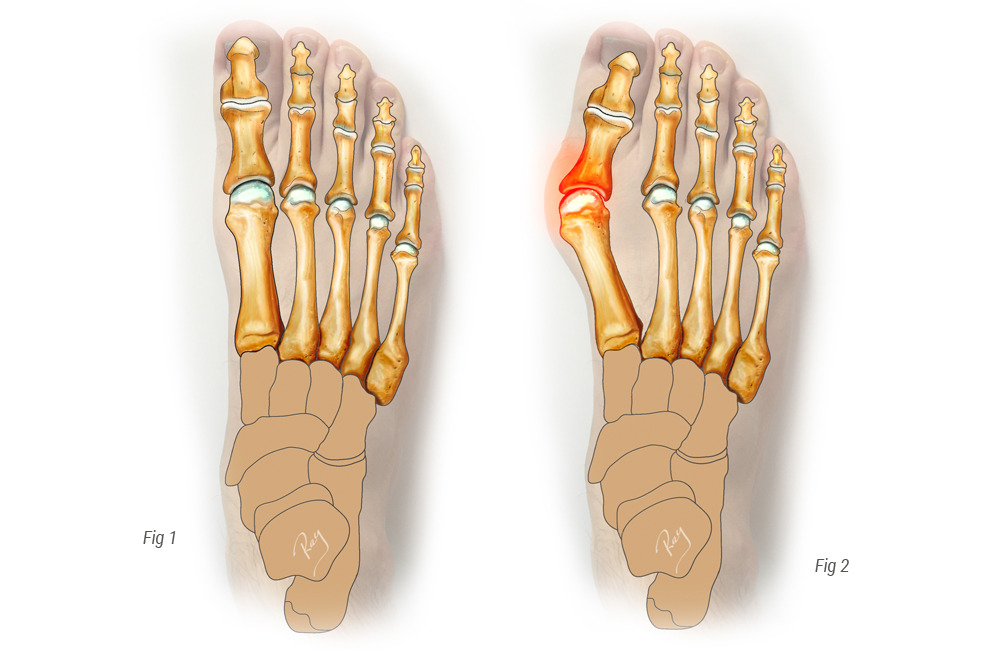

무지외반증

엄지발가락이 바깥쪽으로 휘어지며 발의 균형이 무너져 발바닥에 과도한 압력이 가해지는 질환입니다. 하이힐이나 좁은 신발을 오래 신는 여성에게 흔합니다. 발바닥 앞쪽 통증과 함께 변형이 육안으로 보이는 것이 특징입니다.